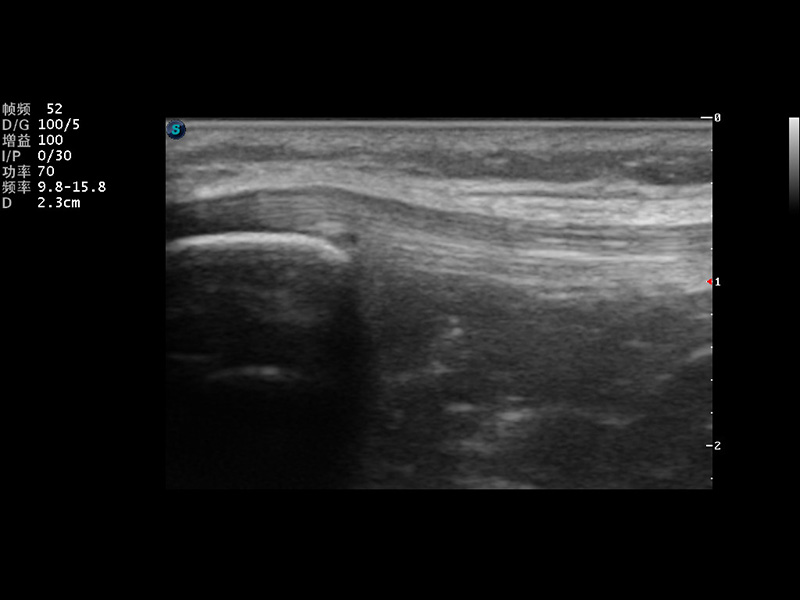

S9便携式彩色多普勒超声诊断仪是开立医疗研发的高端便携彩超设备,外观设计新颖、产品性能卓越。S9在便携超声领域采用了突破传统的触摸屏交互设计,并以先进的软件硬件技术和设计理念,为您带来清晰的图像质量、稳定的工作性能和便捷的操作体验。